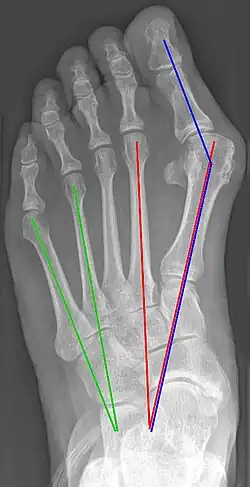

Во всех современных классификациях выделяют несколько степеней заболевания. Основными параметрами по которым оценивают степень вальгусного отклонения первого пальца являются: угол между продольными осями первой и второй плюсневых костей (M1M2) и угол между первой плюсневой и проксимальной фалангой (M1P1). Определение степени деформации необходимо для выбора тактики лечения[4].

1 степень (незначительная) 2 степень (умеренная) 3 степень (выраженная)

M1M2 < 25° M1M2 ≥ 25° M1M2 ≥ 35°

M1P1 < 12° M1P1 ≤ 18° M1P1 > 18°

PASA нормальный или негативный PASA нормальный, негативный или подвывих в плюснефаланговом суставе. PASA негативный или подвывих в плюснефаланговом суставе.

Угол PASA (Proximal articular set angle) — угол наклона суставной поверхности головки M1 по отношению к оси M1.